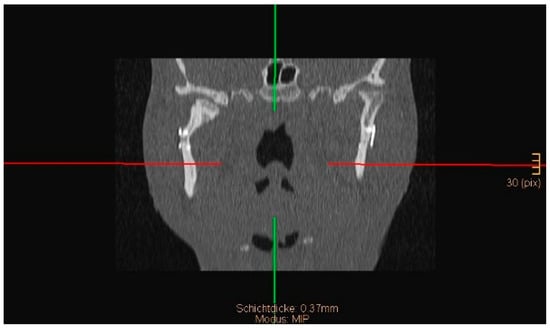

Figure 8 and Figure 9 below show another patient with a non-satisfactory reduction in the condylar neck fracture on the left-hand side due to a lingual gap present at a body fracture (Figure 8 and Figure 9).

Figure 8. Coronal CT scan showing a condylar neck angulation on the left side after ORIF. An anatomical reduction could not be achieved.

Figure 9. Axial CT scan showing the same patient as in Figure 8. A lingual gap is present after ORIF of the mandibular body fracture, contributing to the inability to reduce the condylar fracture correctly.